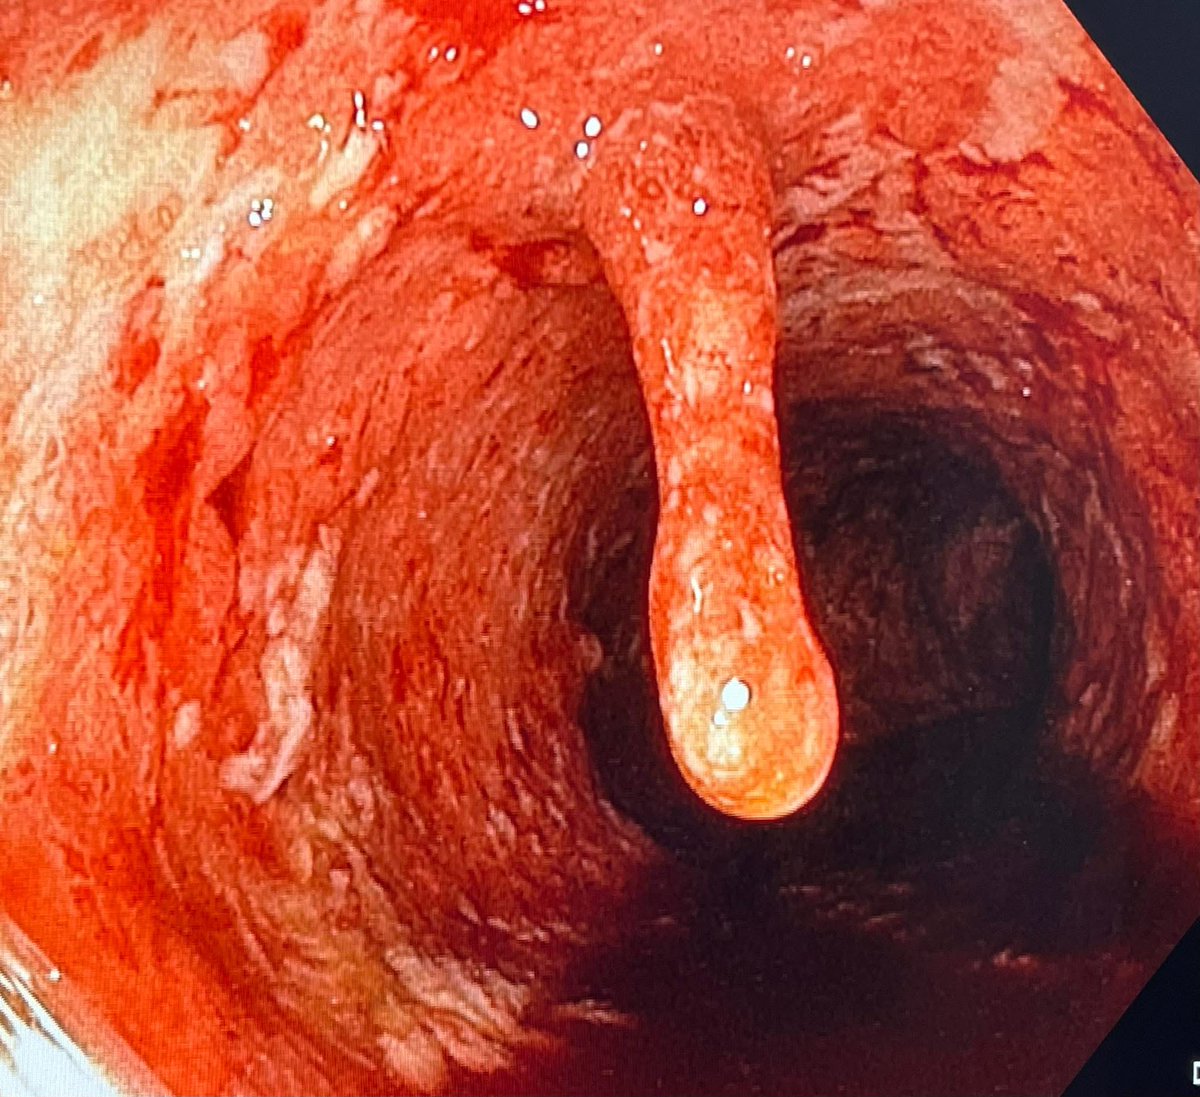

👉Menetrier's disease (also called hypertrophic gastropathy)

👉Diagnosis

Clinical Features:

Epigastric pain

Nausea and vomiting

Weight loss

Peripheral edema (due to hypoalbuminemia)

Anemia (due to mucosal bleeding or poor nutrition)

Laboratory Findings:

Hypoalbuminemia (low serum albumin)

Hypochlorhydria or achlorhydria (due to loss of parietal cells)

Imaging and Endoscopy:

Upper GI endoscopy shows thickened, rugal folds, especially in the body and fundus of the stomach (sparing the antrum)

Biopsies reveal:

Foveolar hyperplasia (mucus cell hyperplasia)

Glandular atrophy

Decreased parietal and chief cells

Minimal inflammation

CT or MRI may show enlarged gastric folds

Histopathology (Gold Standard):

Large, tortuous gastric rugae

Hyperplasia of surface mucous (foveolar) cells

Loss of acid-secreting cells